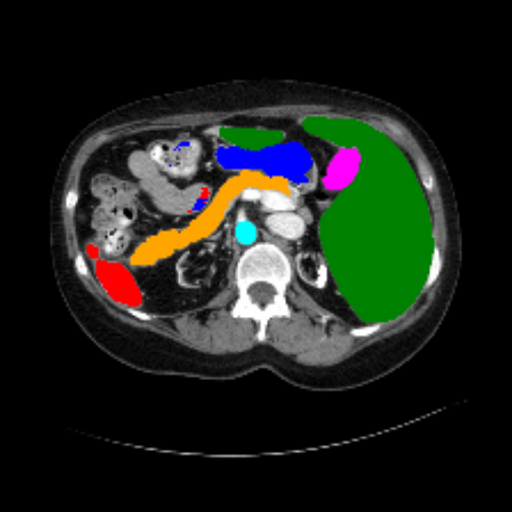

Figure 3 presents a qualitative comparison of segmentation performance on examples from the Synapse, BTCV, ACDC, and ISIC17 datasets. The first two examples (from Synapse) highlight variations in segmentation performance among U-Net, TransUnet, Mamba-Unet, and Swin-Unet. While Swin-Unet performs well in the first example, its performance decreases in the second example, particularly in segmenting the organ highlighted in blue. Additionally, it misclassifies background regions as the class highlighted in orange. In contrast, our approach demonstrates high robustness in segmenting all classes accurately and aligning well with the ground truth masks.

Refer to caption Refer to caption Refer to caption Refer to caption Refer to caption Refer to caption Refer to caption

Slice GT Unet TransUnet Mamba-Unet Swin-UMamba MambaCAFU-V1

Figure 3: Visual comparison of segmentation examples from Synapse (first two examples), BTCV (3-4 examples), ACDC (5th example) and ISIC17 (last example). Columns: input slice, ground truth, Unet, TransUnet, Mamba-Unet, Swin-UMamba, and MambaCAFU-V1.